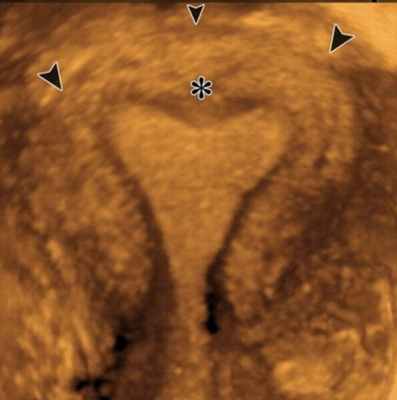

Седловидная матка

Седловидная матка является легкой формой нарушения развития. По форме напоминает седло иногда ассоциируются с формой сердечка. Характеризуется небольшим внутриматочным вдавливанием, тоньше 1 см и расположенным в области дна матки. Образуется в результате почти полного рассасывания перегородки.

Как правило cедловидная матка является находкой во время проведения 3D УЗИ. Эндометрий при седловидной матке является полноценно здоровым и подходящим для имплантации эмбриона. Могут быть определенные риски при беременности, что требует дополнительной бдительности акушер-гинеколога при ведении беременности.